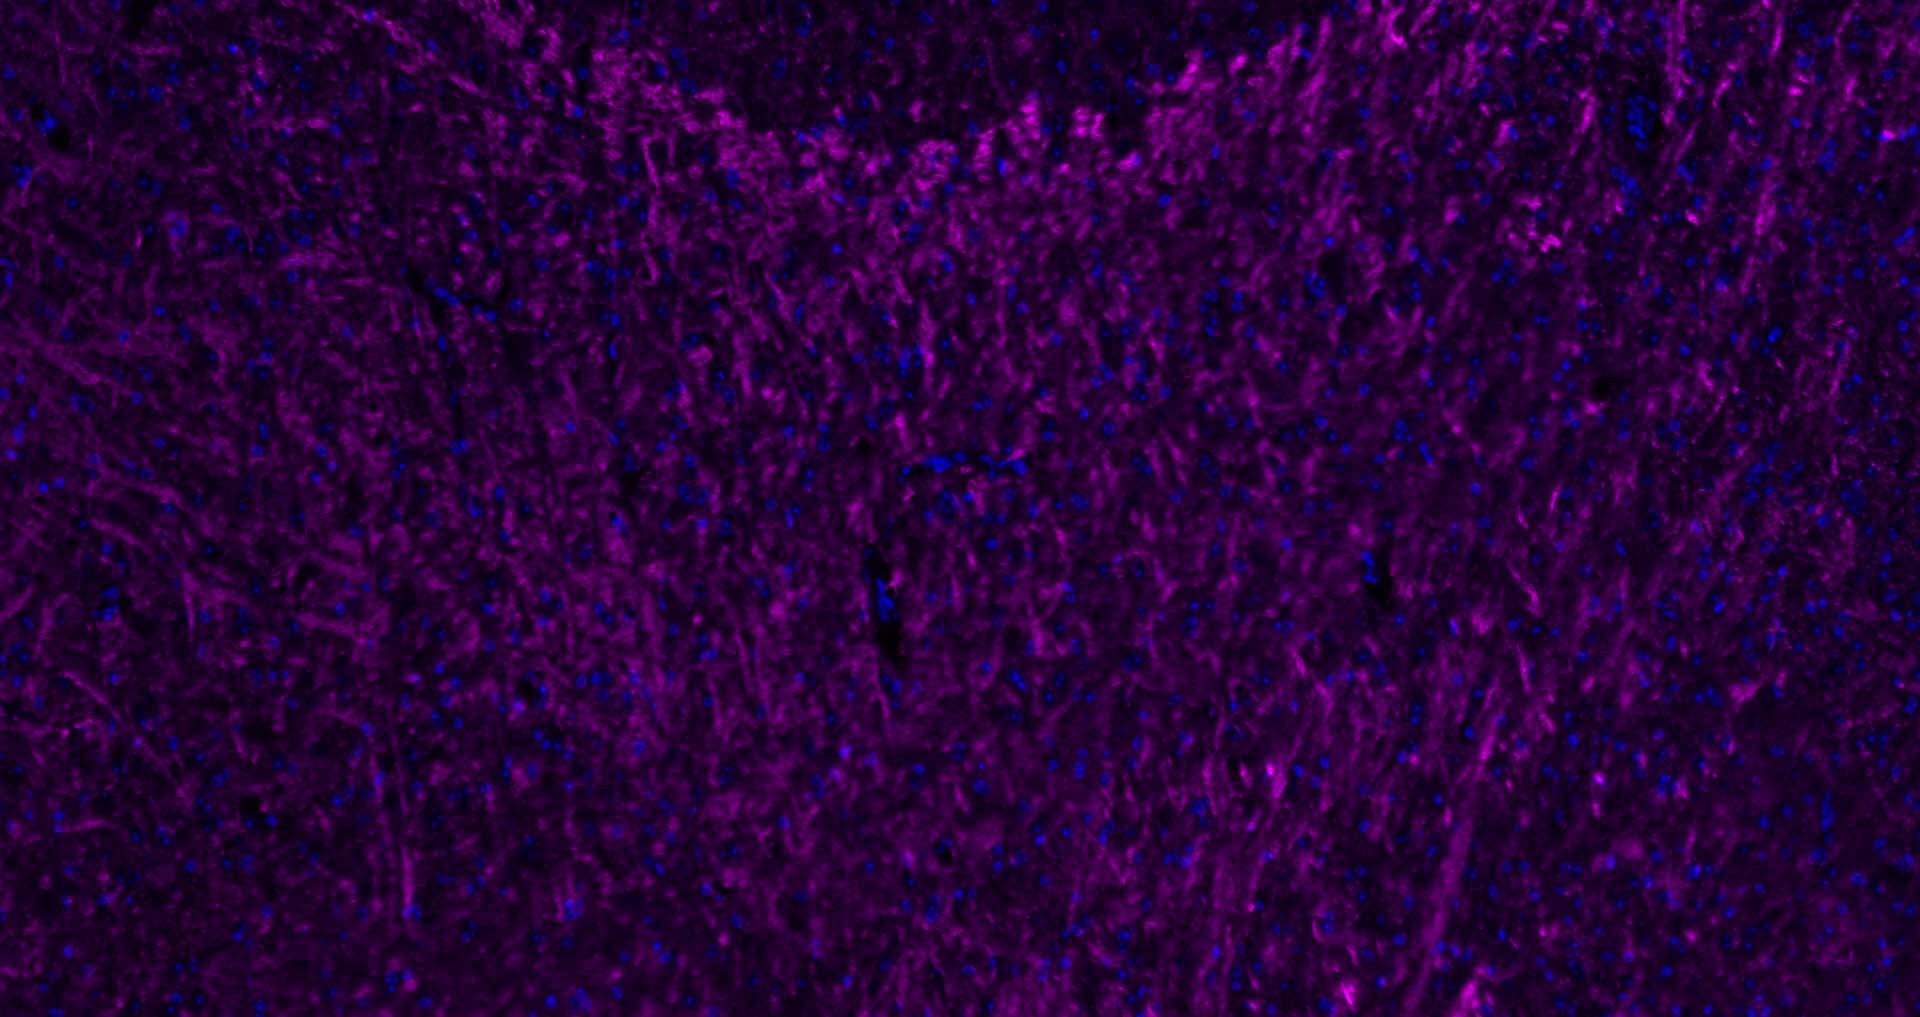

| Verified Activity | 1. 25 μg total protein per Lane of various lysates probed with MBP polyclonal antibody, unconjugated (TMAB-01109) at 1:1000 dilution and 4°C overnight incubation. Followed by conjugated secondary antibody incubation at RT for 60 min. 2. Paraformaldehyde-fixed, paraffin embedded Mouse Cerebrum; Antigen retrieval by boiling in sodium citrate buffer (pH6.0) for 15 min; Antibody incubation with MBP Polyclonal Antibody, Unconjugated (TMAB-01109) at 1:200 overnight at 4°C, followed by conjugation to the SP Kit (Rabbit) and DAB staining. 3. Paraformaldehyde-fixed, paraffin embedded Mouse Cerebellum; Antigen retrieval by boiling in sodium citrate buffer (pH6.0) for 15 min; Antibody incubation with MBP Polyclonal Antibody, Unconjugated (TMAB-01109) at 1:200 overnight at 4°C, followed by conjugation to the SP Kit (Rabbit) and DAB staining. 4. Paraformaldehyde-fixed, paraffin embedded Rat Cerebellum; Antigen retrieval by boiling in sodium citrate buffer (pH6.0) for 15 min; Antibody incubation with MBP Polyclonal Antibody, Unconjugated (TMAB-01109) at 1:200 overnight at 4°C, followed by conjugation to the SP Kit (Rabbit) and DAB staining. 5. Paraformaldehyde-fixed, paraffin embedded Rat Cerebrum; Antigen retrieval by boiling in sodium citrate buffer (pH6.0) for 15 min; Antibody incubation with MBP Polyclonal Antibody, Unconjugated (TMAB-01109) at 1:200 overnight at 4°C, followed by conjugation to the SP Kit (Rabbit) and DAB staining. 6. Paraformaldehyde-fixed, paraffin embedded Human Cerebrum; Antigen retrieval by boiling in sodium citrate buffer (pH6.0) for 15 min; Antibody incubation with MBP Polyclonal Antibody, Unconjugated (TMAB-01109) at 1:200 overnight at 4°C, followed by conjugation to the SP Kit (Rabbit) and DAB staining. 7. Paraformaldehyde-fixed, paraffin embedded Rat Cerebrum; Antigen retrieval by boiling in sodium citrate buffer (pH6.0) for 15 min; Antibody incubation with MBP Polyclonal Antibody, Unconjugated (TMAB-01109) at 1:200 overnight at 4°C. Followed by conjugated Goat Anti-Rabbit IgG antibody (green), DAPI (blue) was used to stain the cell nucleus. 8. Paraformaldehyde-fixed, paraffin embedded Human Cerebrum; Antigen retrieval by boiling in sodium citrate buffer (pH6.0) for 15 min; Antibody incubation with MBP Polyclonal Antibody, Unconjugated (TMAB-01109) at 1:200 overnight at 4°C. Followed by conjugated Goat Anti-Rabbit IgG antibody (green), DAPI (blue) was used to stain the cell nucleus. 9. Paraformaldehyde-fixed, paraffin embedded Mouse Cerebrum; Antigen retrieval by boiling in sodium citrate buffer (pH6.0) for 15 min; Antibody incubation with MBP Polyclonal Antibody, Unconjugated (TMAB-01109) at 1:200 overnight at 4°C. Followed by conjugated Goat Anti-Rabbit IgG antibody (Rose red), DAPI (blue) was used to stain the cell nucleus. 10. Paraformaldehyde-fixed, paraffin embedded Mouse Cerebellum; Antigen retrieval by boiling in sodium citrate buffer (pH6.0) for 15 min; Antibody incubation with MBP Polyclonal Antibody, Unconjugated (TMAB-01109) at 1:200 overnight at 4°C. Followed by conjugated Goat Anti-Rabbit IgG antibody (Rose red), DAPI (blue) was used to stain the cell nucleus. 11. Paraformaldehyde-fixed, paraffin embedded Rat Cerebellum; Antigen retrieval by boiling in sodium citrate buffer (pH6.0) for 15 min; Antibody incubation with MBP Polyclonal Antibody, Unconjugated (TMAB-01109) at 1:200 overnight at 4°C. Followed by conjugated Goat Anti-Rabbit IgG antibody (Rose red), DAPI (blue) was used to stain the cell nucleus. 12. Paraformaldehyde-fixed, paraffin embedded Human Cerebellum; Antigen retrieval by boiling in sodium citrate buffer (pH6.0) for 15 min; Antibody incubation with MBP Polyclonal Antibody, Unconjugated (TMAB-01109) at 1:200 overnight at 4°C. Followed by conjugated Goat Anti-Rabbit IgG antibody (Rose red), DAPI (blue) was used to stain the cell nucleus. 13. Paraformaldehyde-fixed, paraffin embedded Human Left Parietal Lobe; Antigen retrieval by boiling in sodium citrate buffer (pH6.0) for 15 min; Antibody incubation with MBP Polyclonal Antibody, Unconjugated (TMAB-01109) at 1:200 overnight at 4°C. Followed by conjugated Goat Anti-Rabbit IgG antibody (Rose red), DAPI (blue) was used to stain the cell nucleus. ![]() ![]() ![]() ![]() ![]() ![]() ![]() ![]() ![]() ![]() ![]() ![]() ![]() |